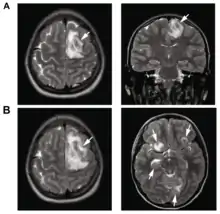

A: T2-weighted MRI showing multiple liqud filled necrotic brain absesss as a result of a Balamuthia mandrillaris infection.

B: T1-weighted MRI showing expansion of the brain lesions 4 days later